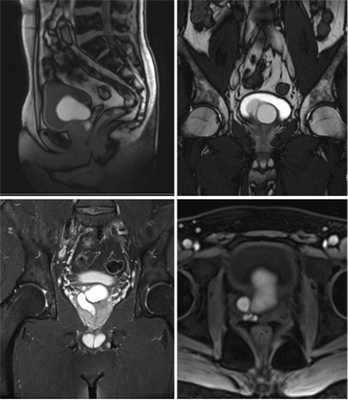

До обращения в клинику урологии МГМСУ пациент неоднократно консультировался в различных специализированных медицинских учреждениях Москвы, а также в урологической клинике Израиля: рекомендовано оперативное лечение в объеме открытой или лапароскопической кистэктомии. Однако в связи с возможным развитием побочных осложнений пациент от оперативного лечения отказался. Дальнейшее обследование, включавшее магнитно-резонансную терапию (МРТ) органов мочевыделительной системы, подтвердило отсутствие правой почки и умеренную гипертрофию левой почки, выявило наличие кисты диаметром 45 мм в области правого семенного пузырька (рис. 2). Рисунок 2. МРТ пациента А. В анализе спермограммы - без патологии.